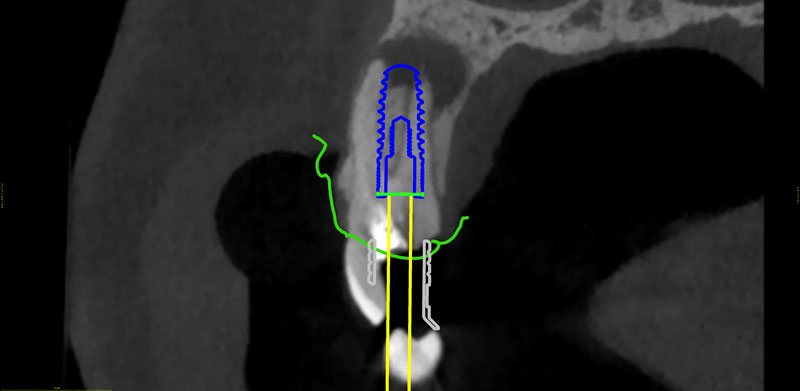

Ψηφιακό πλάνο θεραπείας

Κατευθυνόμενη τοποθέτηση εμφυτευμάτων

Σχεδιασμός χειρουργικού οδηγού

- Ψηφιακό πλάνο θεραπείας

- Κατευθυνόμενη τοποθέτηση εμφυτευμάτων

- Σχεδιασμός χειρουργικού οδηγού